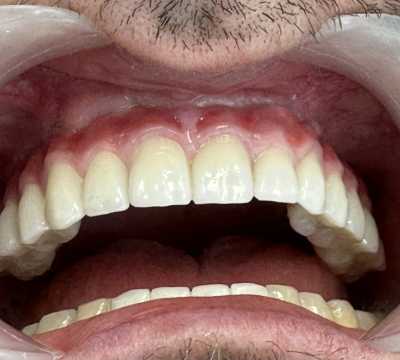

Pacient in varsta de 67 de ani, cunoscut cu boala parodontala severa cu mobilitate avansata a tuturor dintilor, care se prezinta in cadrul clinicii noastre atat din motive functionale, cat si estetice.

Acesta a optat pentru extractia dintilor afectati si protezarea fixa cu ajutorul implanturilor dentare, pacientul dorind respectarea formei si a culorii danturii proprii. Avand in vedere pierderea osoasa importanta, cauzata de patologia pacientului, acesta a necesitat in vederea reabilitarii, atat de sinus lift extern, cat si de aditie osoasa cu os artificial si membrana de colagen.

S-au inserat 10 implanturi dentare la nivel maxilar si 7 la nivel mandibular, pe baza carora s-au realizat protezari fixe metalo-cermice mandibular si ceramica pe zirconiu la nivel maxilar.